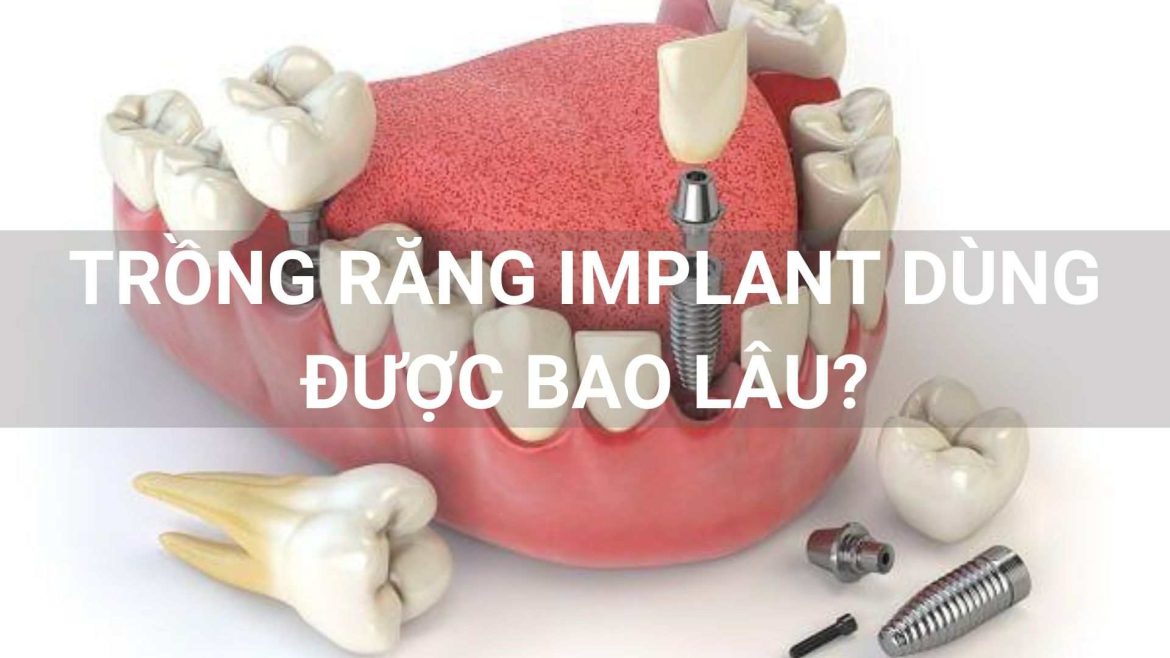

Trồng răng Implant đã không còn quá xa lạ trong thời buổi hiện nay. Tuy nhiên các vấn đề về trồng răng Implant dùng được bao lâu hay trồng răng Implant có bền không vẫn là thắc mắc của rất …